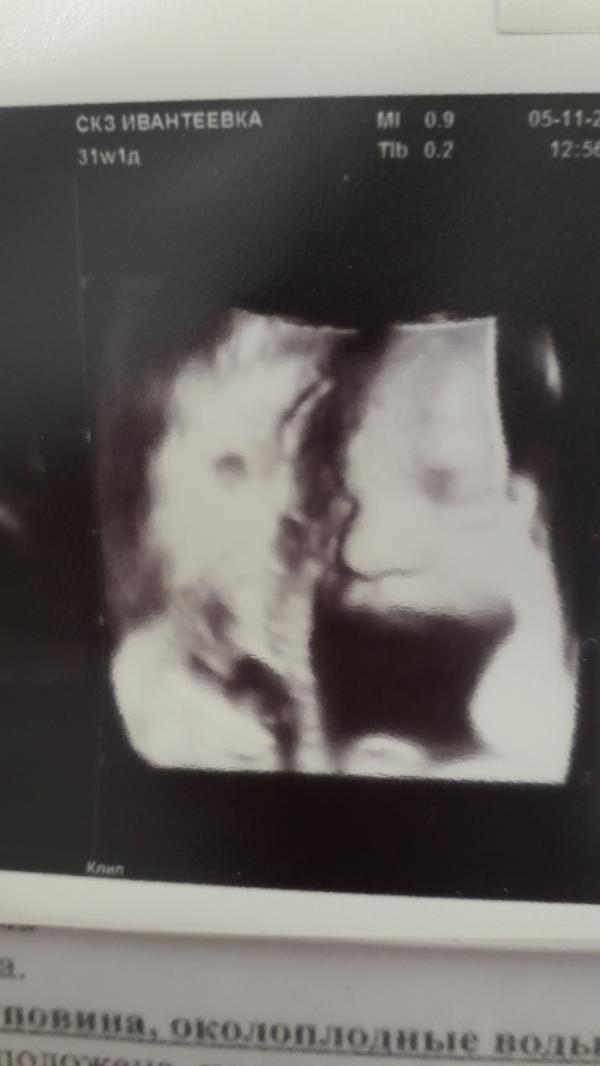

31я неделя, сходили сегодня все вместе на узи 2/3Д. Муж в восторге, говорит будто в кинотеатр сходили)))). Сын всё нюнюкал)

Наш мальчик копия Лёвки)), нос, глаза. Фото не совсем удачно получилось сделать, боком лежал).

Тазовое предлежание, сидит на попе и очень чувствуется как пинает по мочевому, очень часто и голова под грудью мешается, прямо по середине чувствую, дискомфортно бывает(.

Весим 2100, опережаем свой срок на 2 недели. Дату родов также на 31 декабря написала 🙄, не хотелось ...